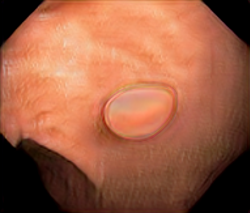

We have used a polyp dataset published with HyperKvasir dataset [51], which consists of polyp findings extracted from endoscopy examinations. HyperKvasir contains polyp images with corresponding segmentation masks annotated by medical experts. We use only this polyp dataset as a case study because of the time and resource-consuming training process of the SinGAN-Seg pipeline. However, the SinGAN-Seg model and pipeline can be used for any segmentation dataset.

A few sample images and the corresponding masks of the polyp dataset in HyperKvasir are shown in Fig 2. The polyp images are RGB images. The masks of the polyp images are single-channel images with white () for true pixels, which represent polyp regions, and black () for false pixels, which represent clean colon or background regions. In this dataset, there are different sizes of polyps. The distribution of polyp sizes as a percentage of the full image size is presented in the histogram plot in Fig 3, and we can observe that there are more relatively small polyps compared to larger polyps. Additionally, a subset of this dataset was used to prove that the performance of segmentation models trained with small datasets can be improved using our SinGAN-Seg pipeline, and the whole dataset was used to show the effect of using SinGAN-Seg generated synthetic images instead of a large dataset which has enough data to train segmentation models. In this regard, this dataset was used for two purposes: